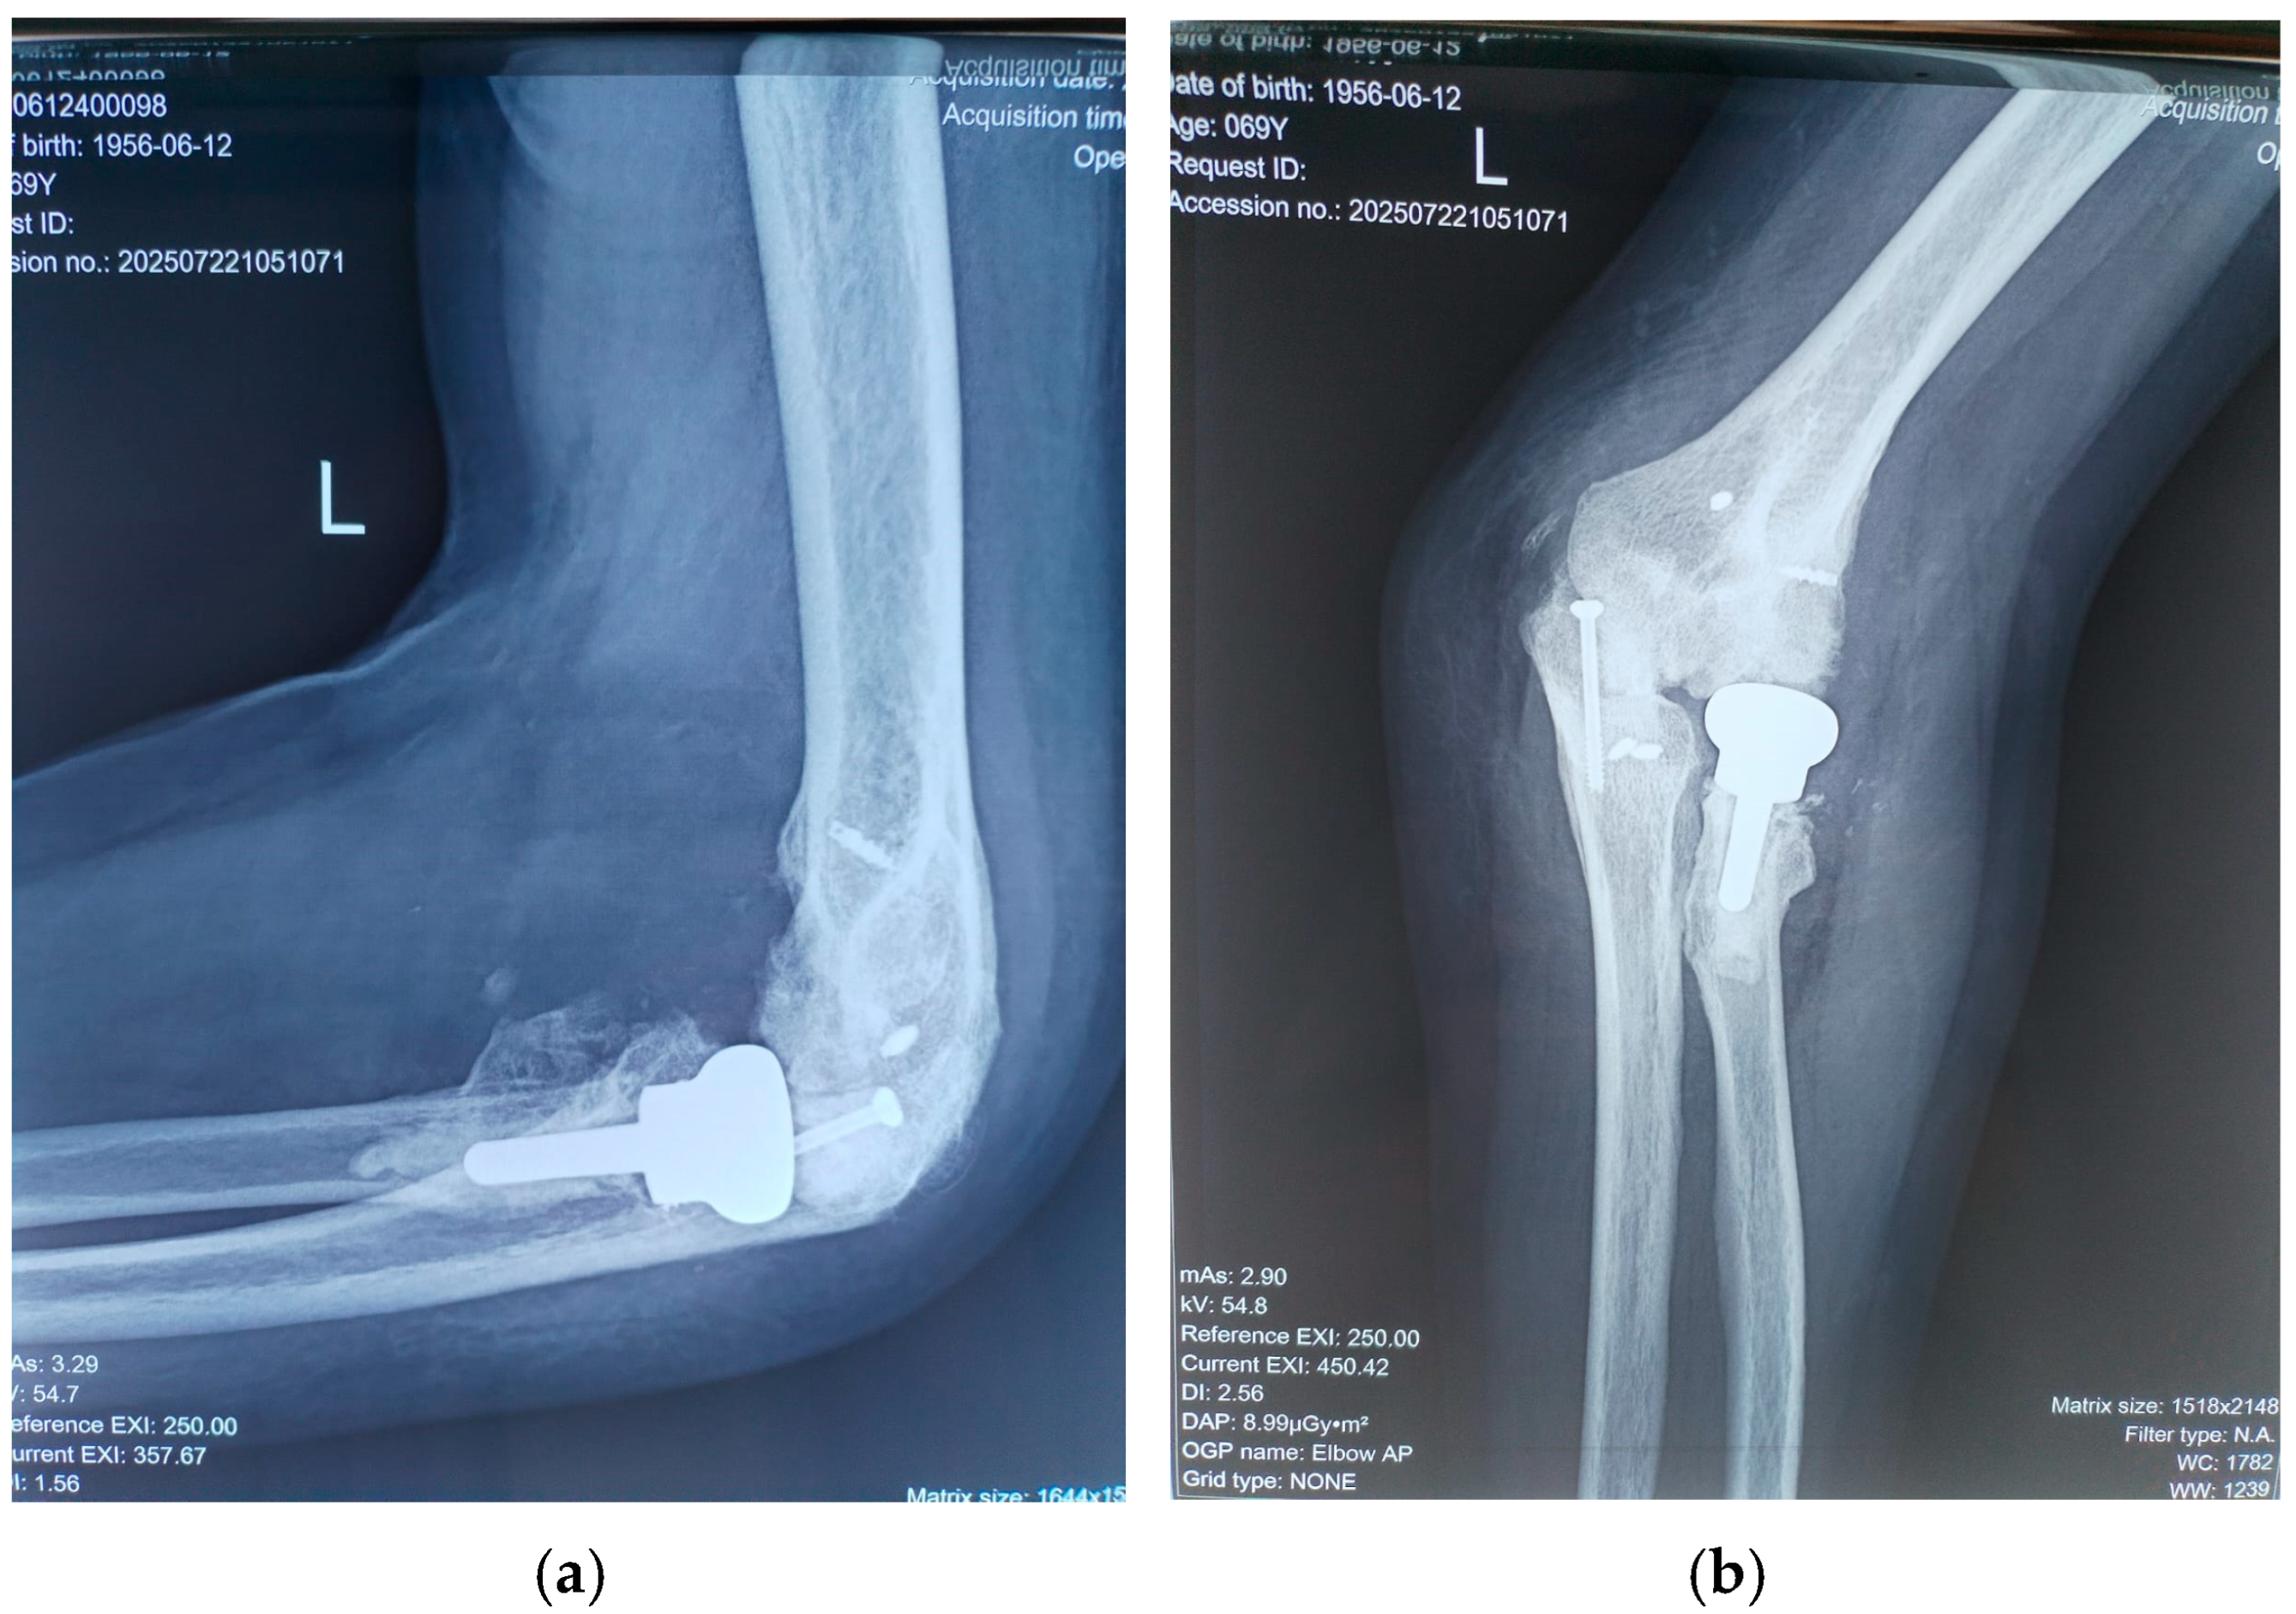

Sutures were removed at two weeks postoperatively. Follow-up assessments occurred at six weeks, three months, and 18 months, at which point the patient’s MEPI score had improved to 95 (Table 2). Between four and six weeks post-surgery, passive exercises were gradually replaced by active movements. No wound infections or ulnar nerve deficits were observed. Follow-up radiographs at 18 months confirmed maintained reduction, proper positioning of the radial head prosthesis, and no recurrence of heterotopic ossification (Figure 5).

Figure 5. (a) Lateral and (b) anterior view of elbow at 18 months after surgery.